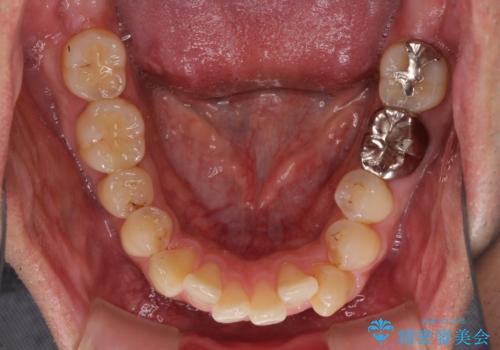

前歯のデコボコと下顎の八重歯 インビザラインによる矯正治療

- 前歯のデコボコや八重歯を気にして来院された患者様です。

インビザラインを用いて、歯列を整えることとしました。

下顎前歯は後戻りを起こしやすいため、舌側を細いワイヤーで固定し、マウスピース型リテーナーで保定を行うこととしました。